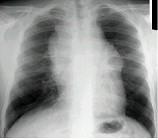

问题 男,17岁,发现颈部肿块1个月,胸片检查、CT检查如图,最可能的诊断为 ( )

选项 A.胸腺瘤 B.畸胎瘤 C.淋巴瘤 D.胸内甲状腺瘤 E.囊状淋巴管瘤

答案 C